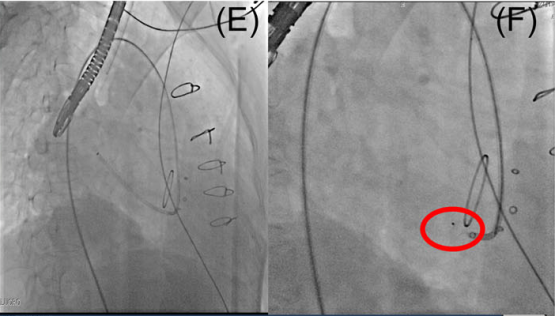

在放置封堵器之前,使用外周球囊扩张瓣周漏,这样做的目的是对形状不规则的漏口进行塑形,是封堵器能够充分的贴合,避免术后的残余漏以及溶血病发症的发生。同时也能够通过球囊扩张的形状来选择封堵器的尺寸。

封堵前后进行多角度对比,瓣膜的工作并未受到影响。